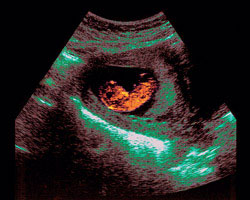

Agora mostramos-te uma ecografia de um feto na semana de gravidez em que te encontras. Também poderás ver um vídeo com o feto em movimento. É, no mínimo, surpreendente!

Ecografia de 11 semanas

Além de detetar possíveis grandes malformações embrionárias, cardíacas, cerebrais e abdominais, na 11ª semana de gravidez uma ecografia irá confirmar as três medidas essenciais que permitem determinar a idade gestacional. Estas são o diâmetro da cabeça, o comprimento do fémur e a circunferência abdominal.